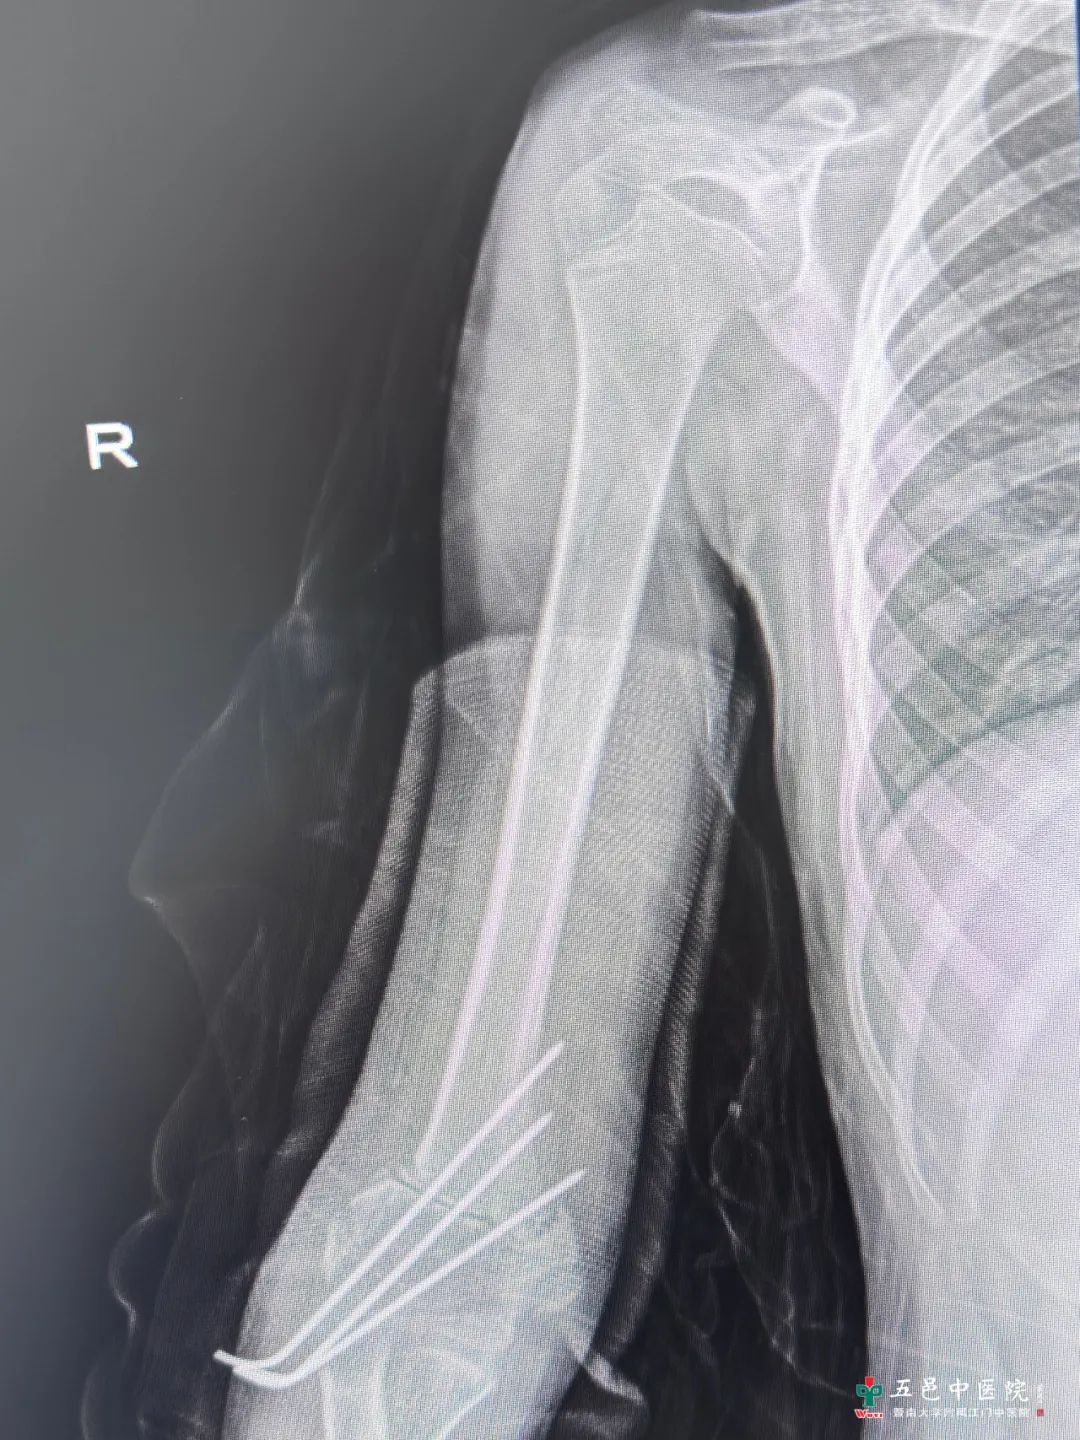

入住医院关节与小儿骨科后,小欣接受了右肱骨髁上三维截骨矫正术,畸形得以矫正,术后1个月查体可见双上肢伸直位携带角基本一致。目前,他在等待拔除内固定,后期通过康复训练小欣有望恢复正常的功能和外观。

图1-术前正位DR(左)

图2-术后正位DR(中)